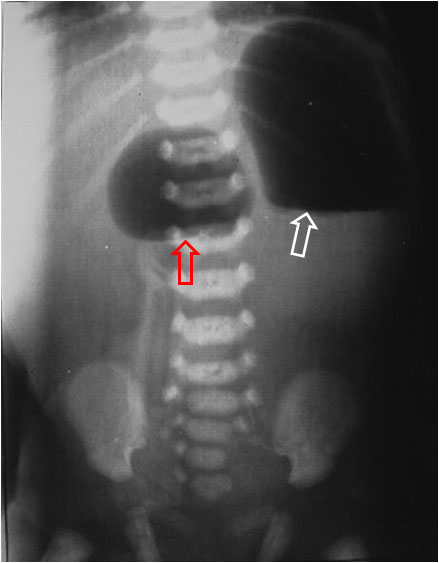

SIGNO DE LA DOBLE BURBUJA

Signo de obstrucción duodenal visible en la radiografía simple de abdomen del neonato, que consiste en la distensión por gas del estómago (flecha blanca) y de la porción del duodeno proximal a la obstrucción (flecha roja). Las causas incluyen: atresia duodenal, páncreas anular, vólvulo intestinal, membrana duodenal, malrotación y vena porta preduodenal.

Este signo también es visible en la ecografía prenatal. En este caso el aspecto ecográfico es el de dos imágenes quísticas correspondientes al estómago y duodeno proximal. Puede verse un ejemplo en http://radiopaedia.org/articles/double-bubble-sign.